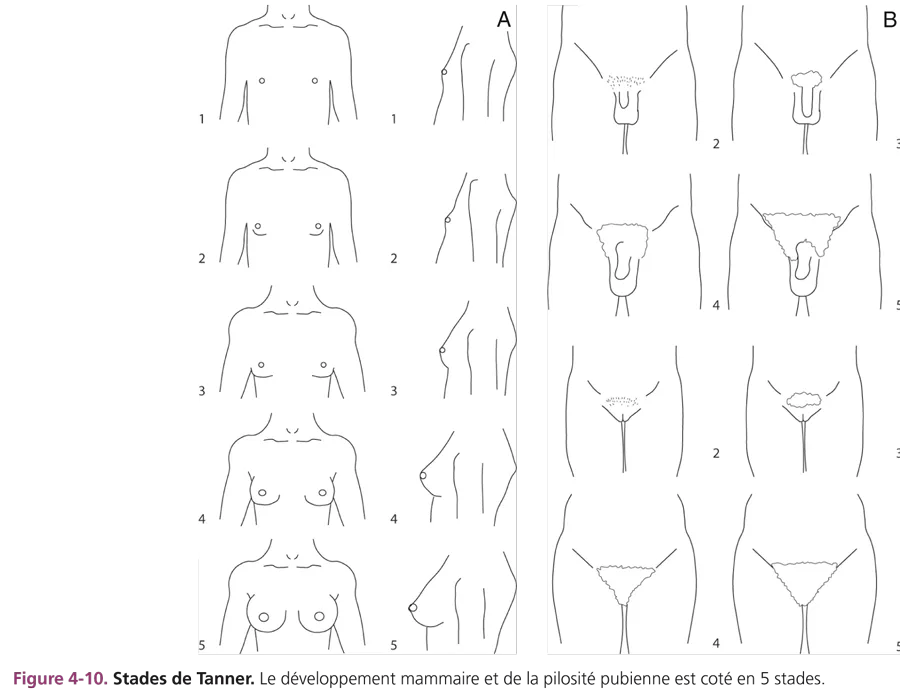

L’apparition des caractères sexuels secondaires survient entre 8,5 et 13 ans chez 95 % des filles et débute par une poussée mammaire. Pour mémoire, chez 95 % des garçons, le début de la puberté dont témoigne le développement testiculaire se situe entre 10 et 13,5 ans. L’accroissement progressif de la pilosité pubienne, le développement mammaire, testiculaire et pénien sont cotés selon les 5 stades de Tanner (fig. 4-10). La durée moyenne entre la poussée mammaire initiale et les menstruations est d’environ 2 ans. Chez le garçon, le développement pubertaire est en moyenne complet en 3 ans. Parallèlement, se produit une accélération de la vitesse de croissance staturale avec une maturation osseuse progressive cotée sur la radiographie de la main selon l’atlas de Greulich et Pyle.